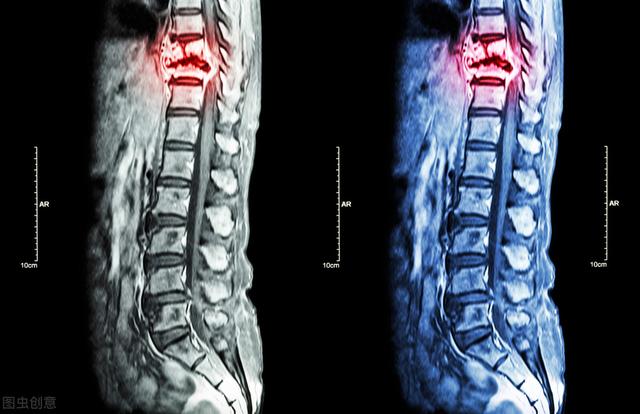

骨転移の磁気共鳴画像法

胸椎に発生した骨転移性癌を示す。

がんによる骨転移患者の痛みには一定の特徴がありますが、一般的な病気と干渉する症状も見受けられます。もし患者が発生した場合、脊椎の骨転移が神経を刺激し、医師や患者が椎間板ヘルニアによって誘発された症状を誤診しやすく、この時、患者として、体に異常があるため、適時に医師の助けを求め、医師として患者とコミュニケーションを図り、比較的質の高い検査を行い、骨転移のリスクを除外しようとする。例えば、高齢者の長期的な腰痛に対しては、レントゲン検査の代わりにMRI検査を行うことをよく勧める。例えば、慢性的な腰痛を持つ高齢者に対しては、レントゲン検査の代わりにMRI(磁気共鳴画像装置)検査を受けるよう勧めることがよくあります。

がんの既往があり、その時点で悪性度が高いと判断されれば、全身骨シンチで骨転移の有無を調べることができる。同時に、転移部位の骨破壊の程度を磁気共鳴検査で明らかにすることができる。